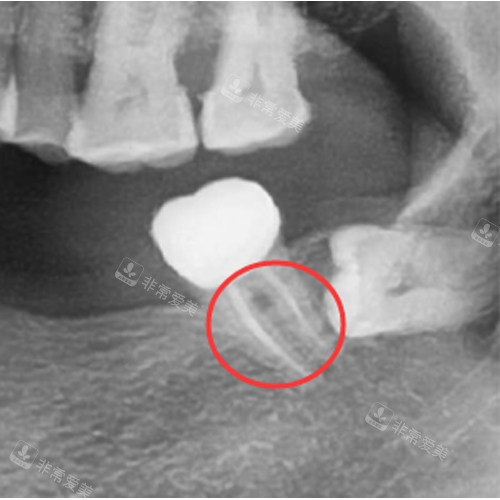

根管治疗治疗图

根管治疗后的牙齿